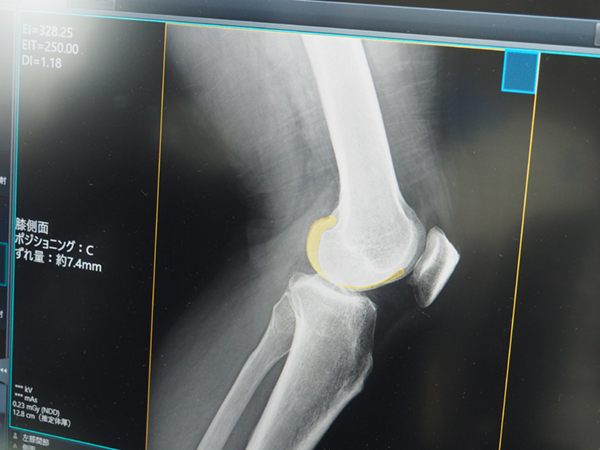

ポジショニング判定支援AI「Positioning-i」は,AIがオーダーと画像の不整合を確認し,膝関節や足関節,肘関節側面などの撮影部位のポジショニングのズレや左右間違いを検知し,再撮影の要否の判断を支援する。また,新たに胸部の正面/側面の対応が追加され,撮影方向間違いの検知も可能になった。これらのAI技術により,再撮影の早期判断や画像の誤送信防止につなげるなど,検査業務の効率化を支援する。

ポジショニング判定支援AI「Positioning-i」ではズレの範囲をわかりやすく表示可能